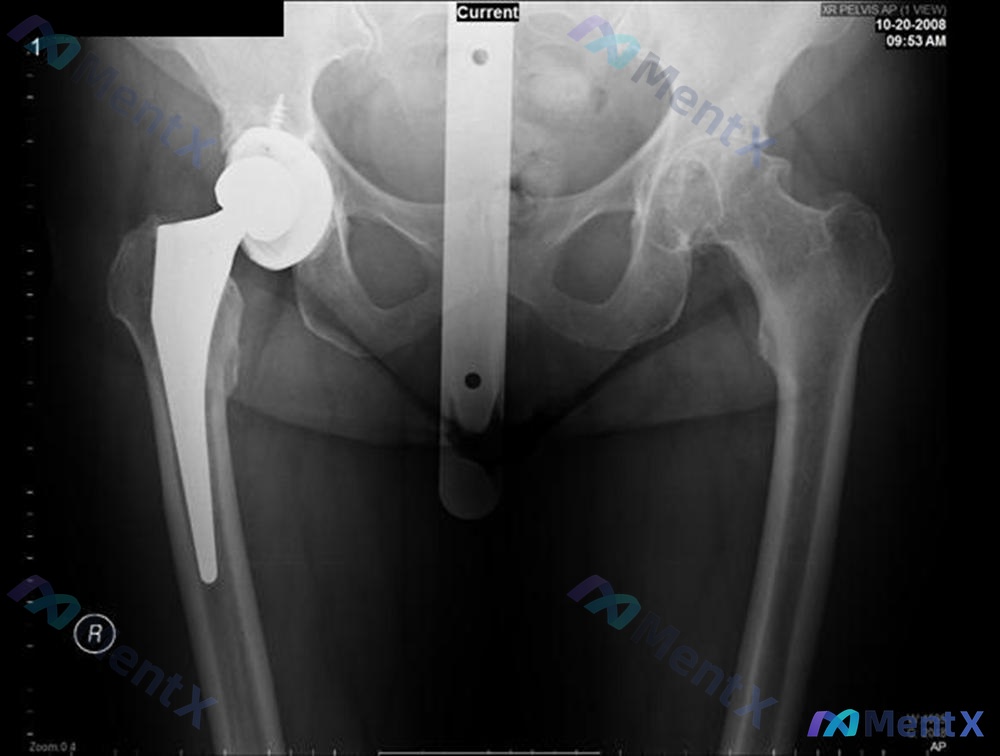

整理到一个骨科病例,有点意思,也有容易被带偏的地方,发出来大家讨论一下。 基本情况: 64岁女性,身体整体健康。 核心病史: 6个月前做了后路右全髋关节置换术(THR),术后到现在已经出现3次后脱位,每次都需要去手术室在麻醉下做闭合复位才能回去。 影像资料: 提供了一张骨盆正位X光片(图A)。 影像...